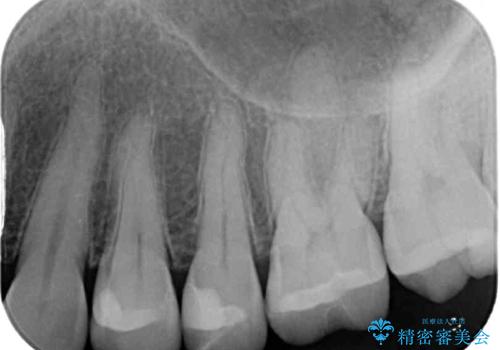

- 銀歯をセラミックにしたいとのことで来院された患者様です。

まず麻酔をして銀歯を外し、むし歯を除去し、形を整えて型取りします。

そして次の来院時、セラミックインレーを装着し、噛み合わせなどの調整を行います。

それを左右に分けて行いました。

インレーを装着するときは、唾液や血液による接着力の低下を避けるためにラバーダム防湿を行いました。